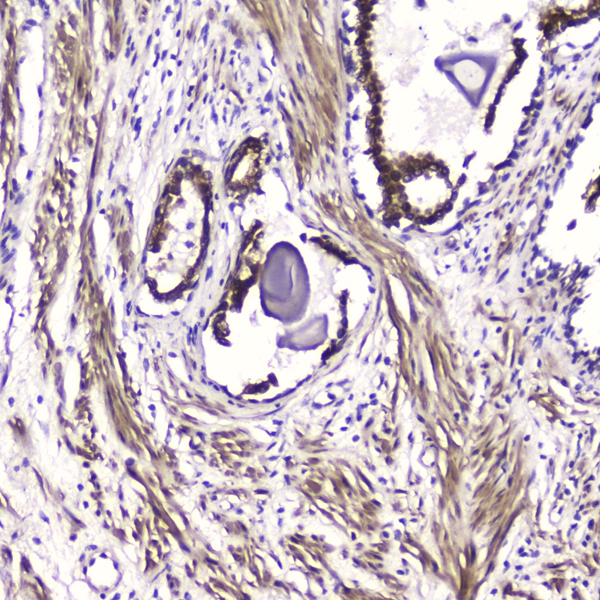

(Figure 3. IHC analysis of ATF4 using anti-ATF4 antibody.ATF4 was detected in paraffin-embedded section of human prostatic cancer tissue. Heat mediated antigen retrieval was performed in citrate buffer (pH6, epitope retrieval solution) for 20 mins. The tissue section was blocked with 10% goat serum. The tissue section was then incubated with 2 ug/mL rabbit anti-ATF4 antibody.ATF4 was detected in paraffin-embedded section of human prostatic cancer tissue. Heat mediated antigen retrieval was performed in citrate buffer (pH6, epitope retrieval solution) for 20 mins. The tissue section was blocked with 10% goat serum. The tissue section was then incubated with 2 ug/mL rabbit anti-ATF4 Antibody overnight at 4 degree C. Biotinylated goat anti-rabbit IgG was used as secondary antibody and incubated for 30 minutes at 37 degree C. The tissue section was developed using Strepavidin-Biotin-Complex (SABC) with DAB as the chromogen.)